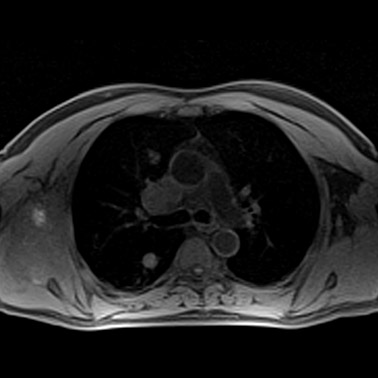

MRT bei Krebserkrankungen (Onkologie)

Die Magnetresonanztomographie (MRT) nimmt bei der Diagnose, dem Staging und der Verlaufskontrolle von onkologischen Erkrankungen einen wichtigen Platz ein.

Auf makroskopischer Ebene lassen sich mit MRT genaue morphologische Informationen (Größe, Form) sowie die Lage der meisten Weichteiltumoren bestimmen. Morphologie und Lage des den Tumor umgebenden, nichtbefallenen Weichteilgewebes sind von lebenswichtiger Bedeutung und bestimmen das Vorgehen bei einer nachfolgenden Strahlentherapie.

Lungentumor 1

Lungentumor 2